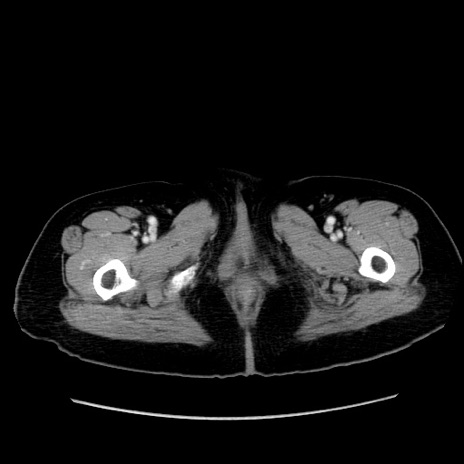

症例19(横断像)

【症例】80歳代女性

【主訴】下腹部痛

【現病歴】約8時間前より下腹部痛の出現あり、救急外来受診。

【既往歴】両側付属器切除

【身体所見】意識清明、下腹部正中に手術痕あり、その部位に一致して圧痛と反跳痛あり。腸蠕動音は亢進。

【データ】WBC 9300、CRP 0.15